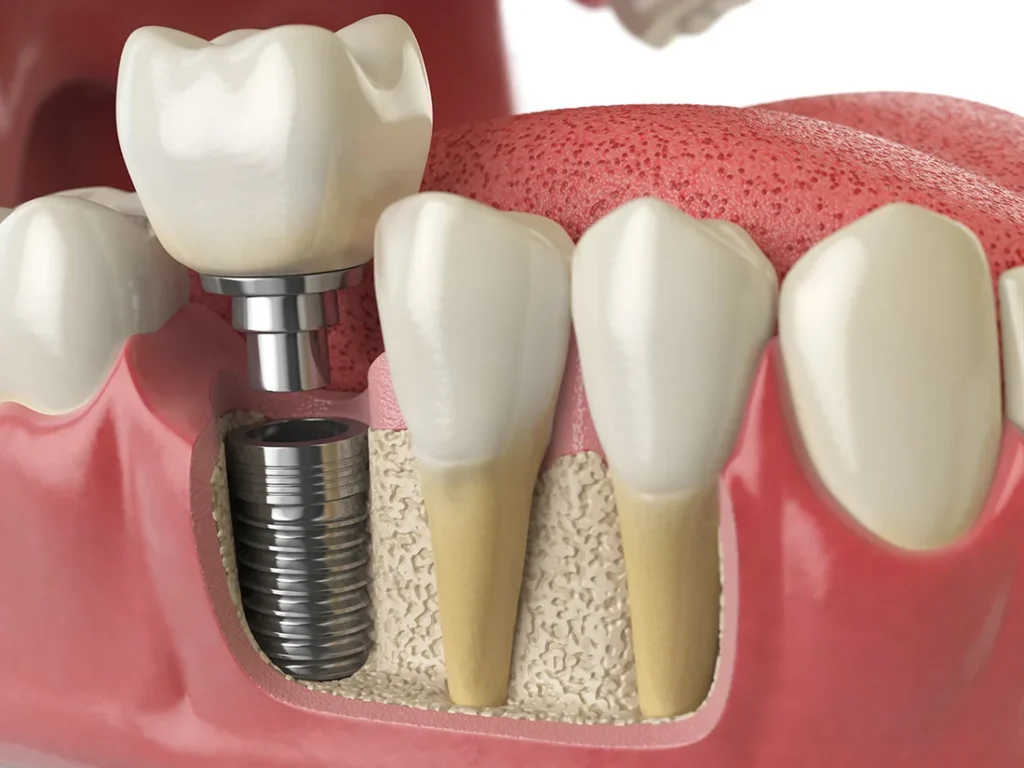

Solutions d’implant dentaire unitaire : retrouvez votre sourire en toute confiance

Perdre une dent peut nuire à la mastication, à la confiance et à la santé buccale. Découvrez comment l’implant dentaire unitaire offre une solution stable et naturelle. Explorez les étapes, les avantages et les coûts des implants dentaires à Montréal avec Chirurgie Buccale Seaforth.